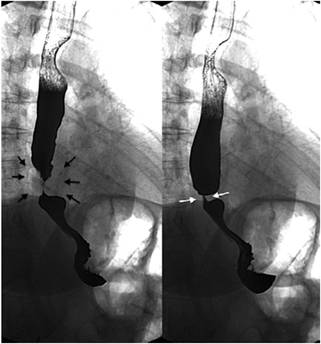

Hernia hiatal

La hernia hiatal es una protrusión del estómago a través del hiato esofágico al tórax que afecta del 10% al 50% de la población, y su diagnóstico y tratamiento tempranos previenen enfermedades de mayor complejidad 11,12. En la evaluación final del esofagograma, se debe identificar la presencia de hernias hiatales, definidas como un tamaño mayor de 2 cm entre la unión esofagogástrica y el hiato diafragmático (si es menor de 2 cm, la herniación es fisiológica) 11,12. El 95% de las hernias primarias son de tipo I (deslizadas) y los tipos II, III y IV se agrupan en las hernias paraesofágicas (más del 90% son de tipo III, y las menos comunes corresponden al tipo II). El reparo laparoscópico es el estándar de tratamiento, y el esofagograma es de utilidad para establecer el tamaño de la hernia, puesto que se requiere una amplia disección esofágica, el cierre adecuado del hiato (posible uso de malla) y un mecanismo antirreflujo 11,12 (Figura 4).